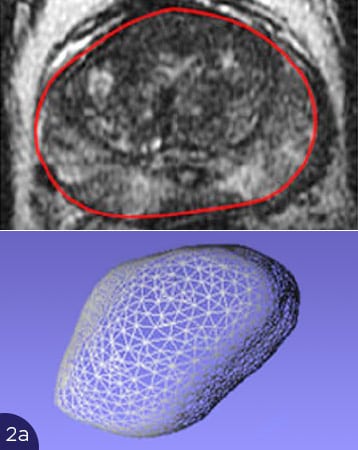

Die Abbildungen zeigen die Probleme mit der Überlagerung von US und MRT-Bildern. In Abb. 2(a) ist die Form der Prostata im MRT-Bild gezeigt, oben als Querschnitt (rote Umrandung), unten als 3D-Darstellung der gesamten Prostata. In Abb. 2b bis 2d sind Querschnitte der Prostata im Ultraschall dargestellt (oben, rote Umrandungen), unten die entsprechenden 3D-Volumina. Je nach Füllung der Blase oder Andruck des Ultraschalltransducers im Rektum verformt sich die Prostata stark. Eine Übereinstimmung mit dem MRT-Querschnitt ist nicht zu erreichen. Somit ist eine korrekte Überlagerung der US- und MRT-Bilder nicht möglich. Ein Karzinomherd käme auf dem Ultraschall an anderer Stelle zur Darstellung als auf dem MRT-Bild, eine gezielte Biopsie wäre nicht möglich.